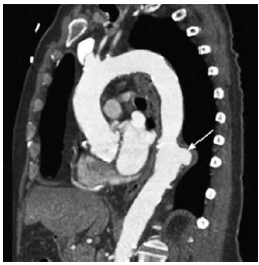

Homem, 60 anos, hipertenso, apresenta dor em dorso de forte intensidade e início súbito. FC: 90 bpm. PA: 200x120 mmHg. Realizou-se a tomografia computadorizada de aorta a seguir.

(BRAUNWALD, E. et al. (Ed.) Tratado de Doenças Cardiovasculares. 11 Ed. Rio de Janeiro: Editora Elsevier, 2022. 2 vol)

Com base no que revela o exame, a hipótese diagnóstica é: